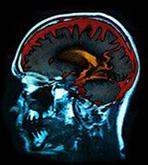

Aβ→酸化ストレス→セラミド、コレステロール代謝異常→神経細胞死→アルツハイマー病